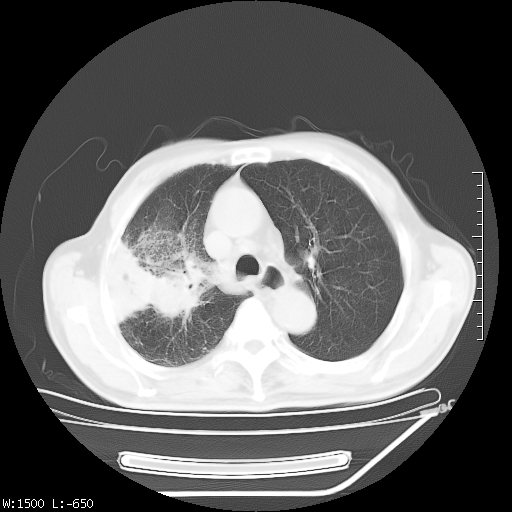

标题: CT23994:男、72、咳嗽、气短两月余,近来消瘦。 [打印本页]

标题: CT23994:男、72、咳嗽、气短两月余,近来消瘦。

tb可能性大(双肺均可见片状密度增高灶,其内可见低密度空洞)。

右上肺大片状密度增高影,与胸膜关系密切,内见低密度透亮影,胸膜下可见三角形不张影,左下肺沿支气管走形结节影,纵膈内淋巴结显示。考虑结核并疤痕性不张可能性大,建议穿刺活检,排除肺泡癌。